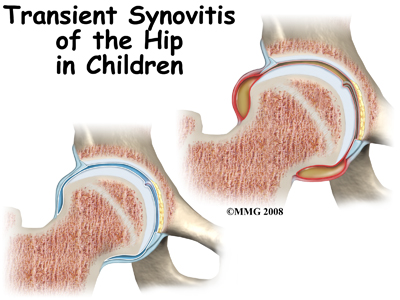

The hip is a ball-and-socket joint. A tough lining called the synovium covers it. The ball of the joint is the end of the thigh bone, called the femur. Like other ends of bones in children, the ball has an area called a growth plate. A growth plate has cells that produce new bone. The growth plate is weaker than other parts of the bone. This makes this area more likely to fracture.

In children from two to ten years old, the most common cause of hip pain is (TS). This involves swelling or inflammation of the synovium of the hip. The synovium is a tough covering of the joint. Often, the child will have had a cold or viral infection just before the hip pain started. Transient synovitis usually lasts ten days. It generally gets better with minimal treatment.

As mentioned above, transient synovitis often happens after having a cold or viral infection.

Transient synovitis usually responds to anti-inflammatory medication and rest. Symptoms generally improve after 10 days, with an eventual return to activity.